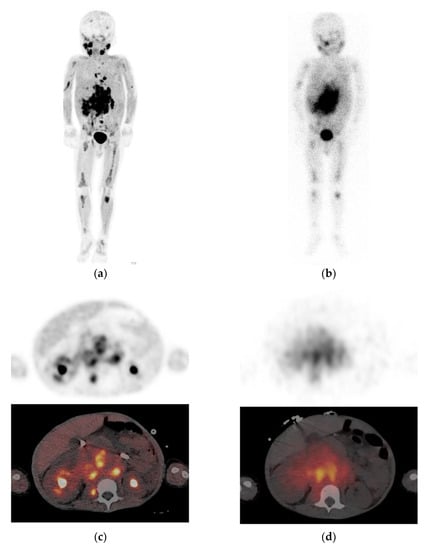

- Kong, G.; Hofman, M.S.; Murray, W.K.; Wilson, S.; Wood, P.; Downie, P.; Super, L.; Hogg, A.; Eu, P.; Hicks, R.J. Initial experience with gallium-68 DOTA-octreotate PET/CT and peptide receptor radionuclide therapy for pediatric patients with refractory metastatic neuroblastoma. J. Pediatric Hematol. Oncol. 2016, 38, 87–96. [Google Scholar] [CrossRef]

- Gains, J.E.; Aldridge, M.D.; Mattoli, M.V.; Bomanji, J.B.; Biassoni, L.; Shankar, A.; Gaze, M.N. 68Ga-DOTATATE and 123I-MIBG as imaging biomarkers of disease localisation in metastatic neuroblastoma: Implications for molecular radiotherapy. Nucl. Med. Commun. 2020, 2, 1169–1177. [Google Scholar] [CrossRef]

- Telli, T.; Lay Ergün, E.; Volkan Salanci, B.; Özgen Kiratli, P. The complementary role of 68Ga-DOTATATE PET/CT in neuroblastoma. Clin. Nucl. Med. 2020, 45, 326–329. [Google Scholar] [CrossRef]